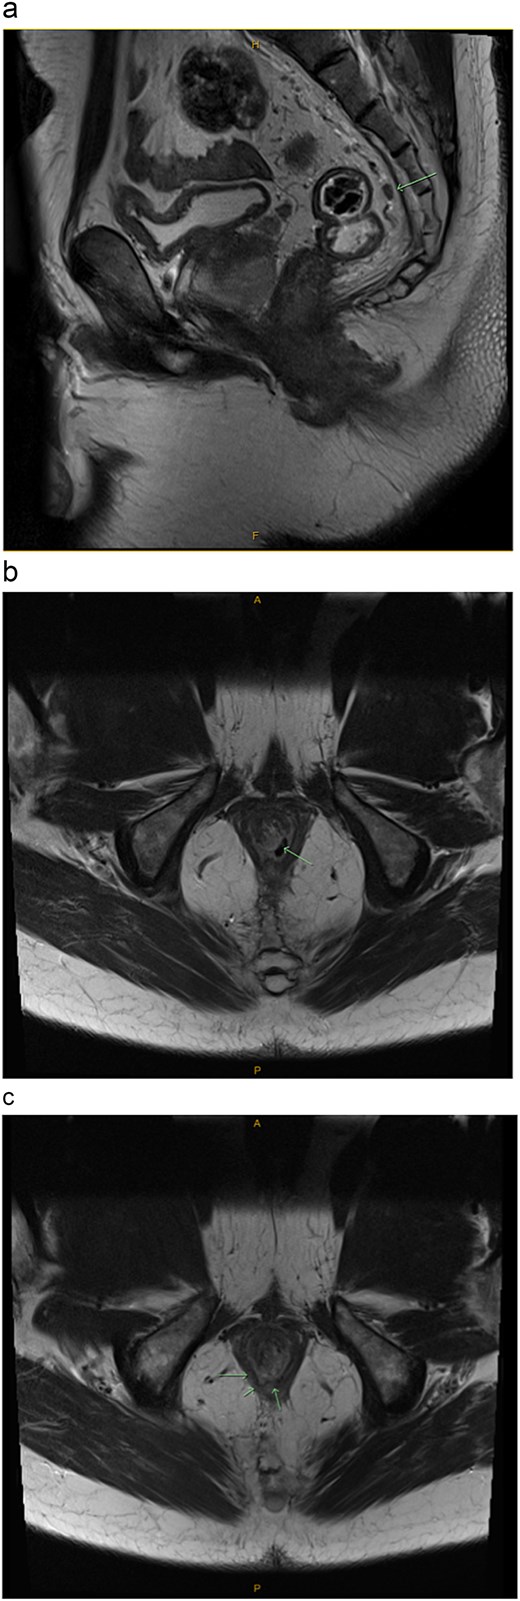

Multiplanar T1 and T2 weighted magnetic resonance imaging (MRI) of the rectum showed abnormal signals, mainly mucosal, based at the anal sphincter complex with extension into the inferior rectal mucosa. There was associated induration and ulceration at the level of the sphincter muscle in the 7 o’clock position (Fig. 4a–c).

Pelvic MRI with contrast enhancement (T1 and T2 weighted imaging including DWI). (a) Sagittal view: Evidence of a single, small mesorectal lymph node (arrow), but no suspicious mesorectal lymphadenopathy. (b) Transverse view: Evidence of a single, small mesorectal lymph node (arrow), but no suspicious mesorectal lymphadenopathy. (c) Transverse view: Mucosal based high T2 signal involving the anal sphincter complex with focal induration/ulceration noted at the level of the sphincter muscle at 7 o’clock (arrows). Extension into the inferior rectus mucosa.